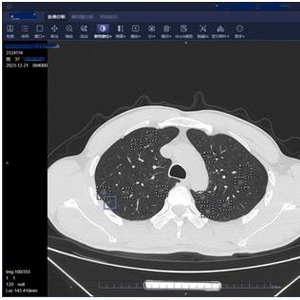

37岁的胡军(化名)最近做了个胸部CT,检查结果显示,其双肺长了557个磨玻璃结节,最大的直径1.2厘米。

“我从医快20年了,甄别过许多肺结节,这次遇到的病例非常特殊。”医生说,这些结节均大于3毫米,随机分布,密密麻麻。

胡军告诉医生,他3年前就查出多发性肺部结节,这几天出现咳痰、胸闷等症状。肺结节人工智能软件提示,其双肺竟有557个磨玻璃结节,其中高危的有26个。